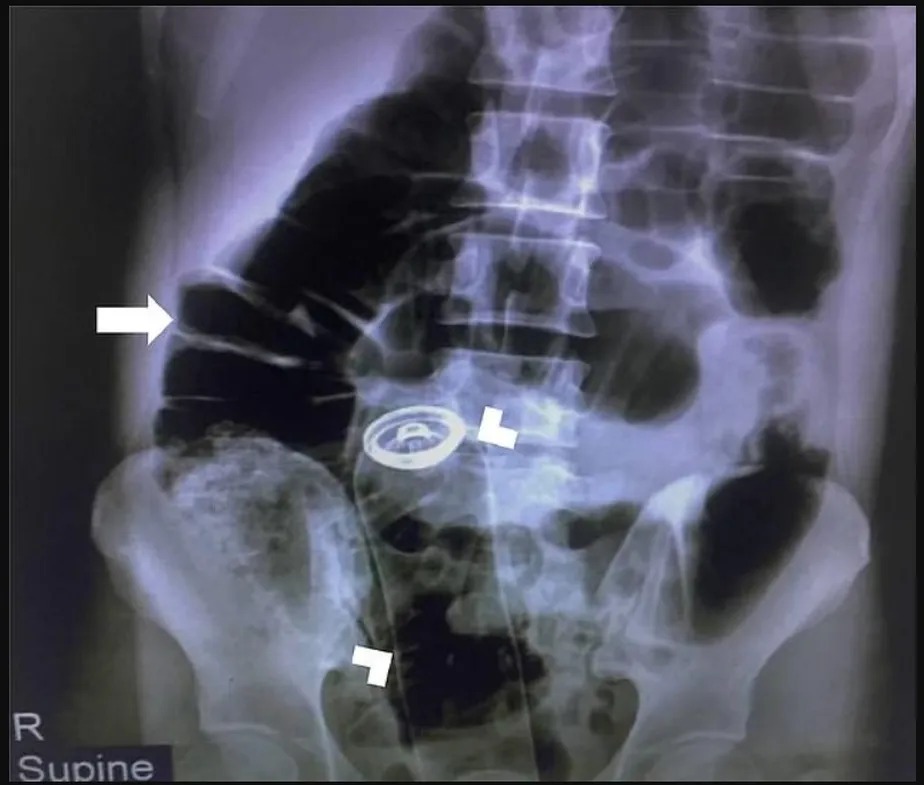

Um homem iraniano de 30 anos precisou passar por uma cirurgia para retirar um tubo de desodorante do estômago duas horas após usá-lo como objeto sexual.

O homem chegou ao hospital com dores estomacais “agonizantes” e confessou que havia inserido o objeto no ânus. Foi feito um raio x para encontrar o tubo, que foi removido cirurgicamente do estômago. Ele ficou um dia em observação no hospital e teve que passar por uma consulta com um psiquiatra antes de ter alta.